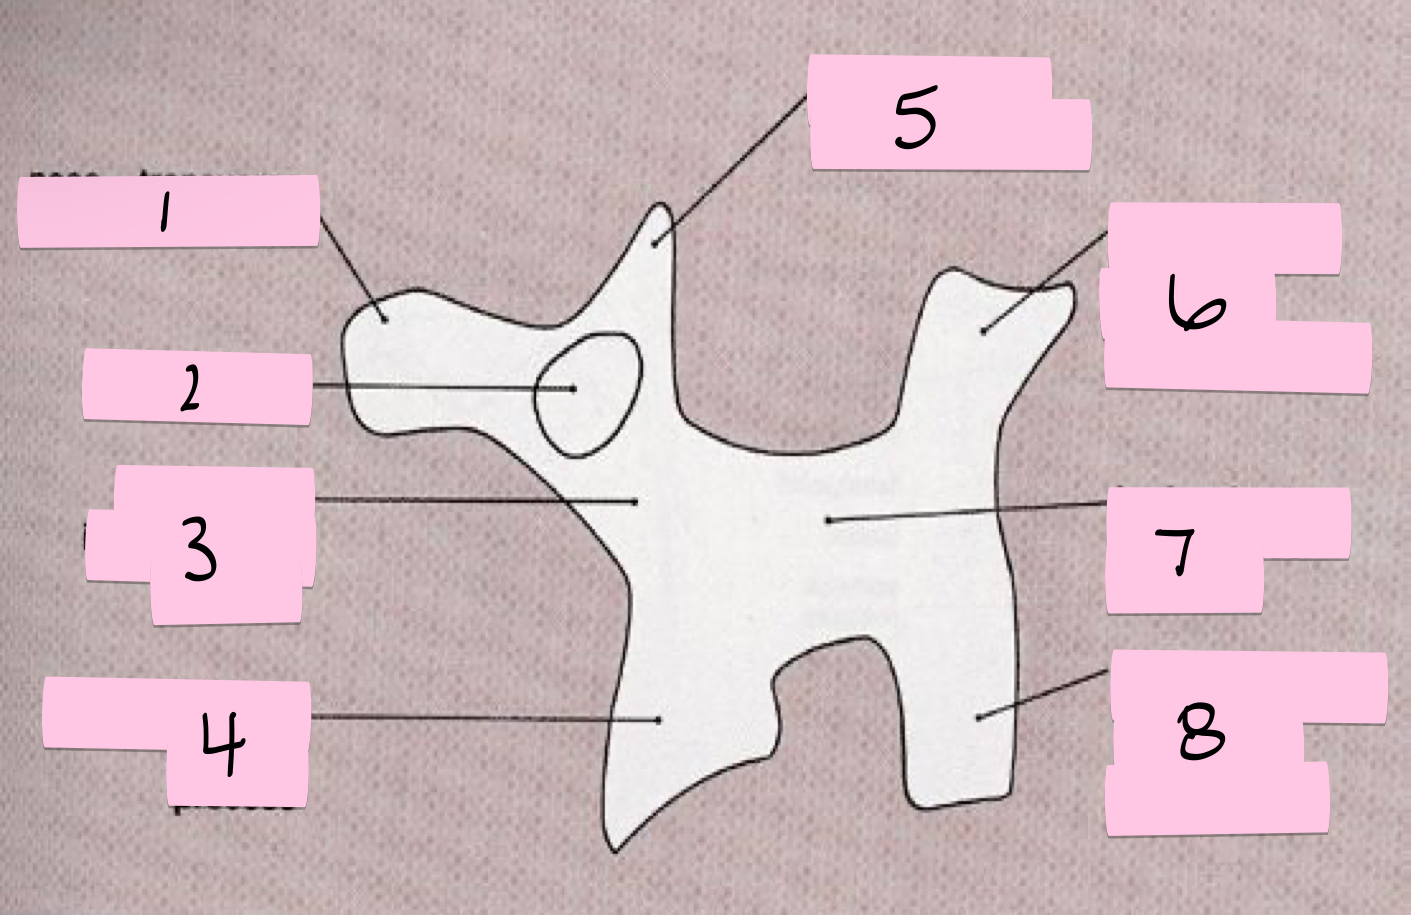

What is 1 pointing to?

Nose- Transverse process

What is 2 pointing to?

Eye- Pedicle

What is 3 pointing to?

Neck- Pars interacticularis (isthmus)

What is 4 pointing to?

Foreleg- Inferior articular process

What is 5 pointing to?

Ear- Superior articular process

What is 6 pointing to?

Tail- Superior articular process of opposite side

What is 7 pointing to?

Body- Lamina and spinous process

What is 8 pointing to?

Hindleg- Inferior articular process of opposite side